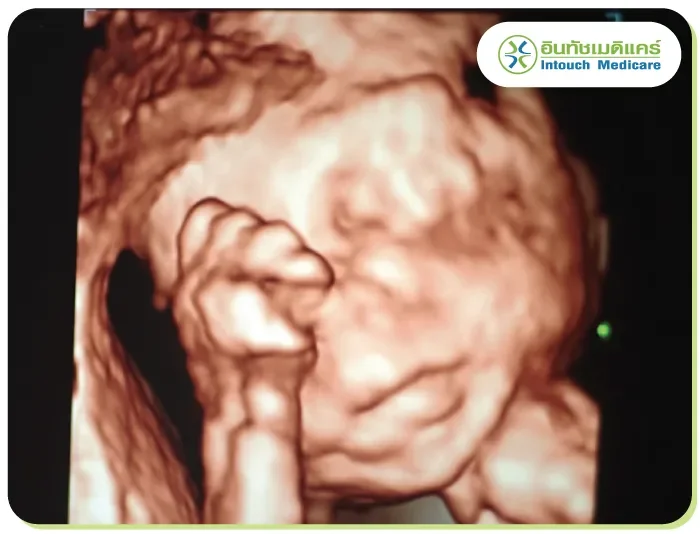

จะแสดงภาพให้เห็นทั้งความกว้าง ความสูง และความลึก โดยการรับสัญญาณคลื่นเสียงที่สะท้อนออกมา ผ่านการวิเคราะห์ด้วยโปรแกรมคอมพิวเตอร์ จึงได้ภาพที่มีรายละเอียดชัดเจน เสมือนจริงกว่าแบบ 2 มิติ

จะคล้ายกับแบบ 3 มิติ แต่จะมีการประมวลผลที่ซับซ้อนขึ้น โดยการนำภาพแบบ 3 มิติมาแสดงผลเรียงต่อกันจนเกิดเป็นภาพเคลื่อนไหวเสมือนจริงแบบ Real- time เห็นรายละเอียดได้อย่างชัดเจน นิยมนำมาใช้ในทางการแพทย์มากขึ้น

อัลตร้าซาวด์ท้องหรือการตรวจครรภ์ (Obstretics) ตรวจเพื่อคำนวณวันคลอด ภาวะการตั้งครรภ์แฝด การตั้งครรภ์นอกมดลูก ตรวจความแข็งแรง ตรวจหาความพิการแต่กำเนิดของทารก ในสมอง ไขสันหลังหัวใจหรือส่วนอื่นๆ ของร่างกาย ของทารกในครรภ์ ตรวจปริมาณน้ำคร่ำ ตำแหน่งของรก รวมทั้งสามารถดูเพศและประเมินน้ำหนักของเด็กได้อีกด้วย

บอกอายุครรภ์ได้ รู้การเคลื่อนไหวและอัตราการเต้นของหัวใจของทารก การตรวจแบบ 4 มิติ จะช่วยตอบโจทย์มากกว่า ซึ่งสถานพยาบาลเอกชนจะมีบริการแบบ 4 มิติ ราคาสบายกระเป๋าให้คุณแม่เลือกใช้บริการตามที่ต้องการได้

จะเห็นได้ว่าการอัลตร้าซาวด์นั้น มีความจำเป็นในทางการแพทย์เป็นอย่างมาก ทั้งกับการตรวจเพื่อคัดกรองโรคต่างๆ รวมทั้งช่วยให้คุณแม่ได้เห็นใบหน้าและการเคลื่อนไหวของเจ้าตัวเล็กตั้งแต่อยู่ในครรภ์